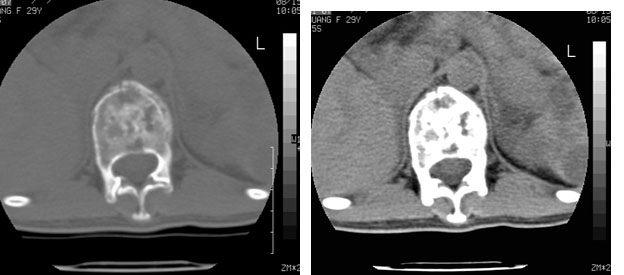

标题: CT10087:女,29岁,多发肿瘤样病变。

车祸致t12压缩性骨折,行ct扫描意外发现椎体多发肿瘤样病变,建议加拍骨盆平片,患者平常无症状。

脾及椎体多发占位病变.

脾脏及椎体多发占位病变。首先考虑淋巴瘤,其次骨髓瘤。建议查本周氏蛋白

椎体多发性溶骨性破坏,部分融合,椎旁无软组织肿块、椎间隙正常,t12 压缩,脾脏增大,其内示多发低密度影,首先考虑多发性骨髓瘤。病人较年轻,平素无异常,转移瘤可能性小。